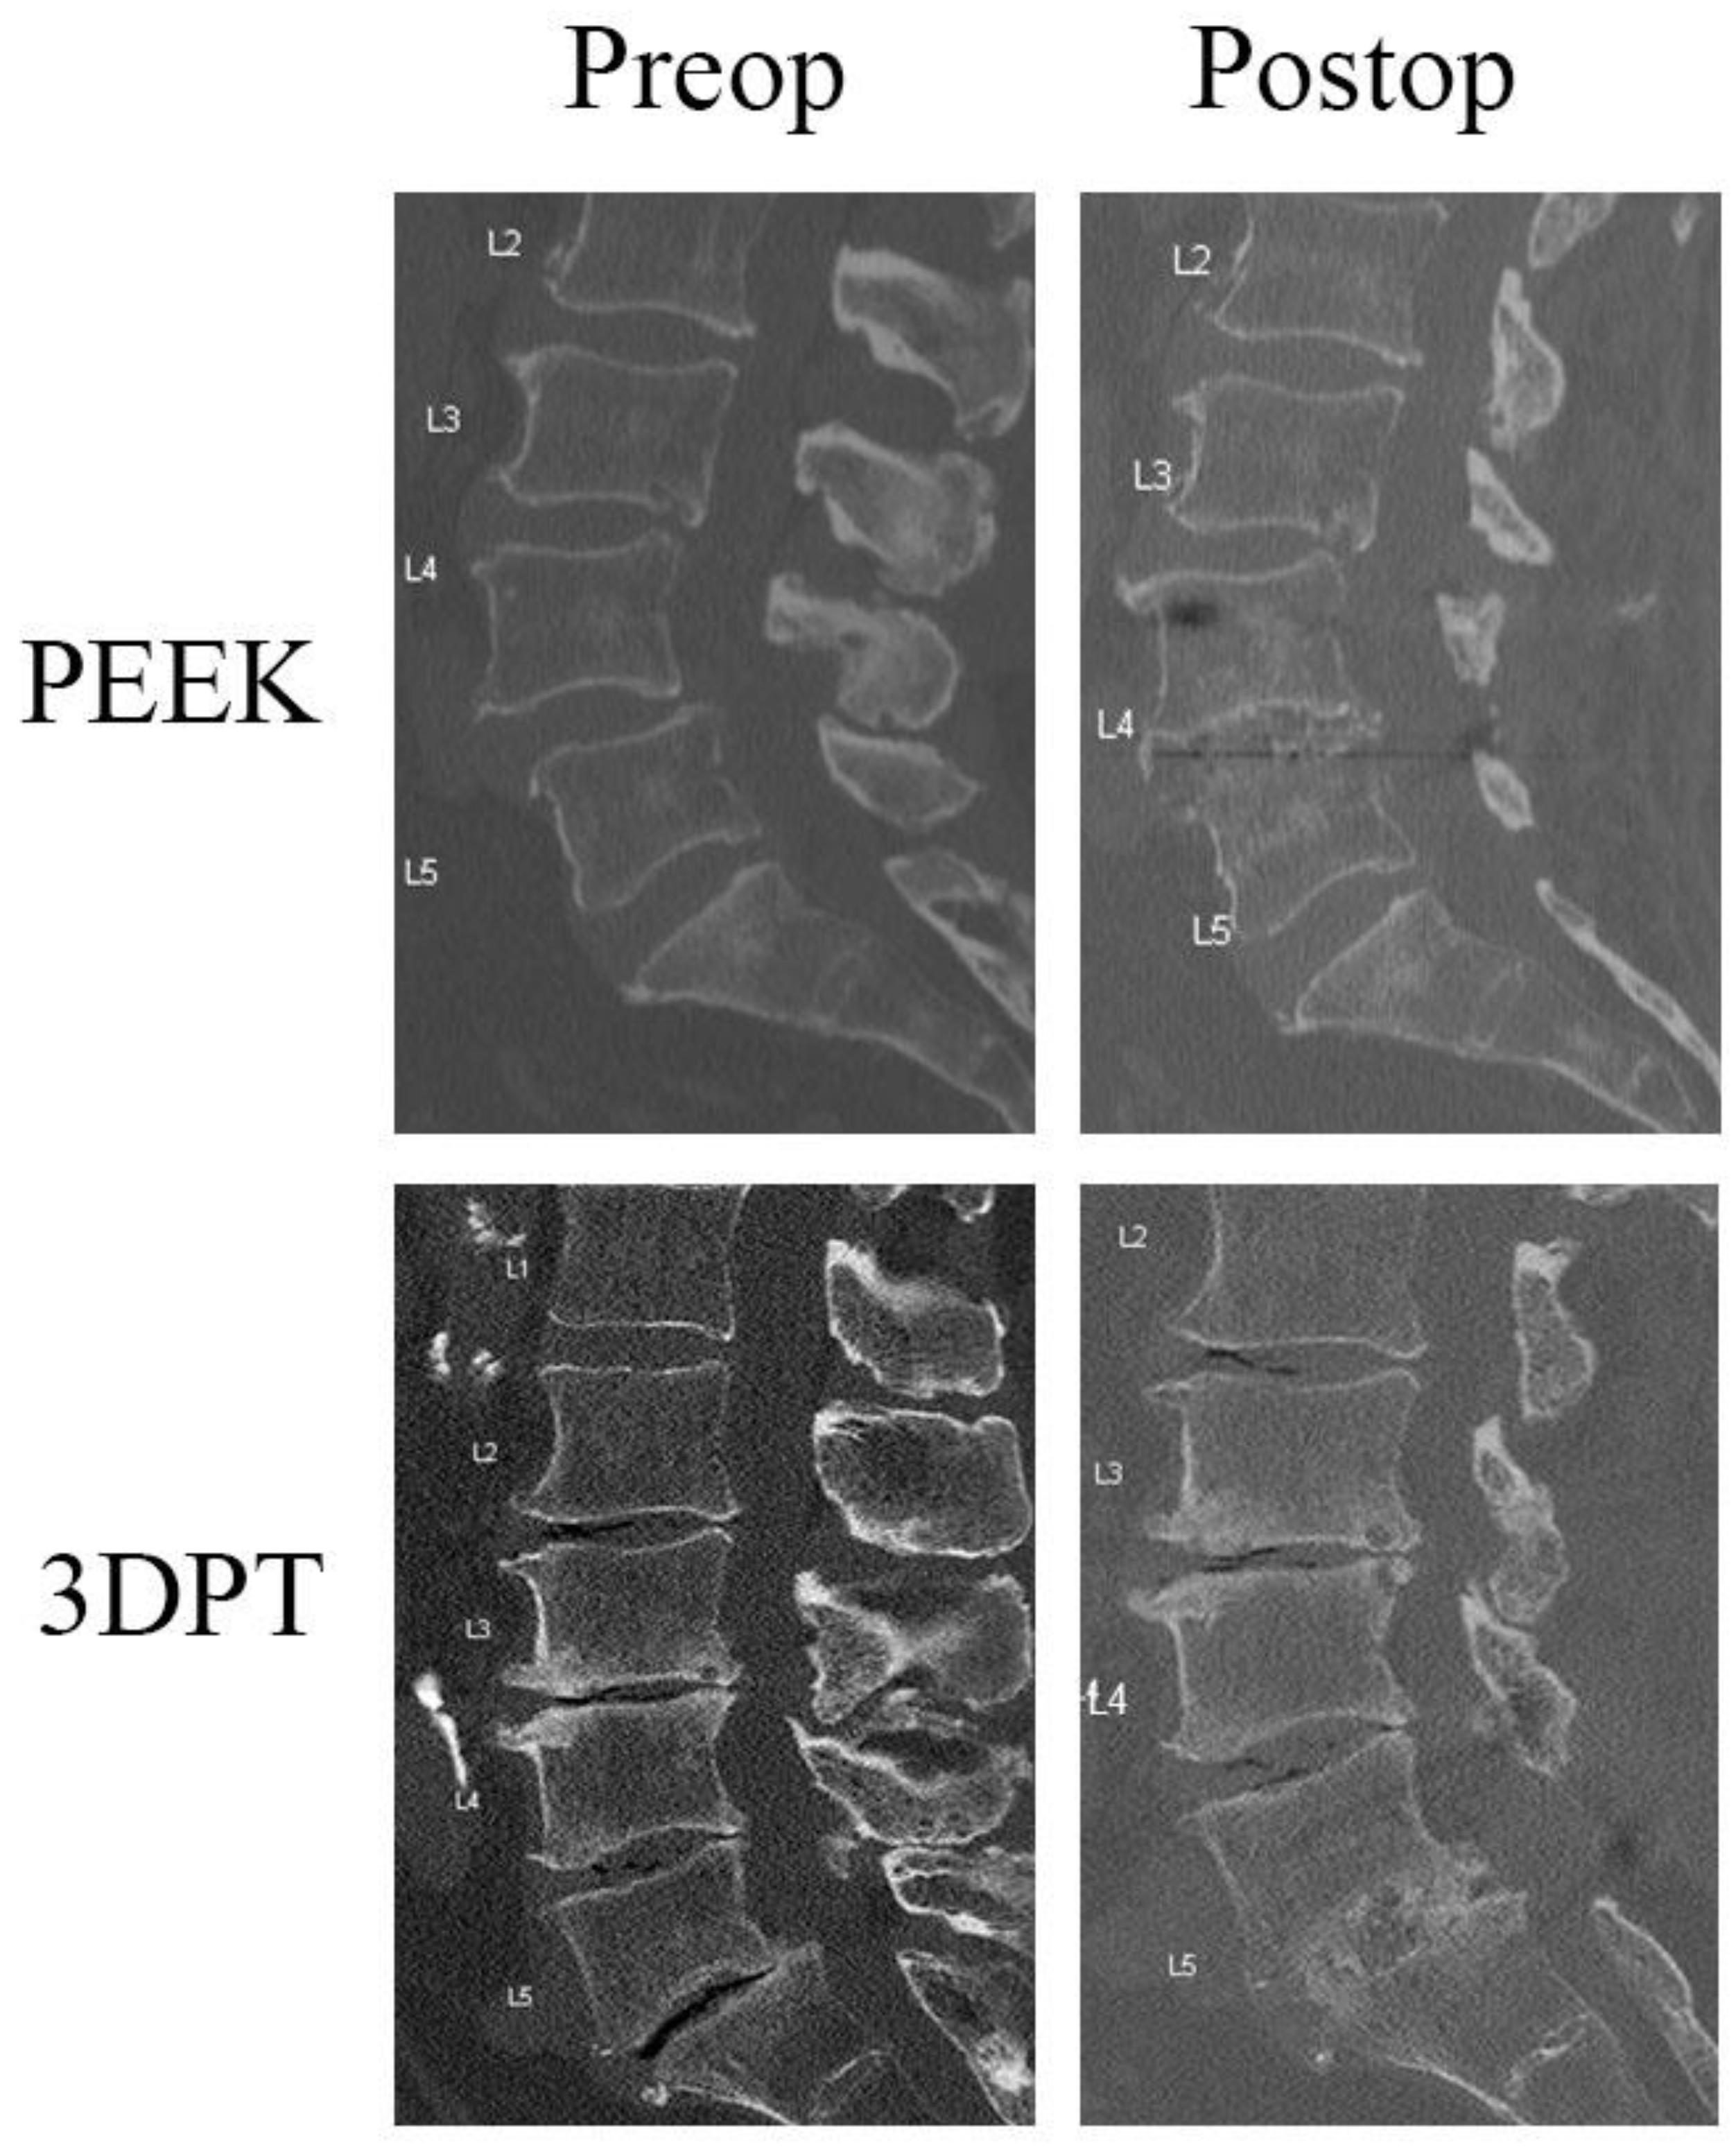

3.3. Radiographic Analysis